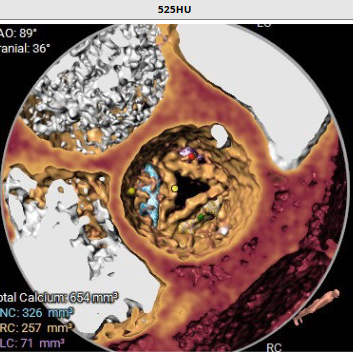

患者术前CT分析:患者主动脉瓣为三叶式,瓣叶重度钙化伴增厚;左侧冠脉开口9.1mm稍低;主动脉弓角度偏小。

瓣环

开口面积

左冠高度

钙化积分

外周血管通道